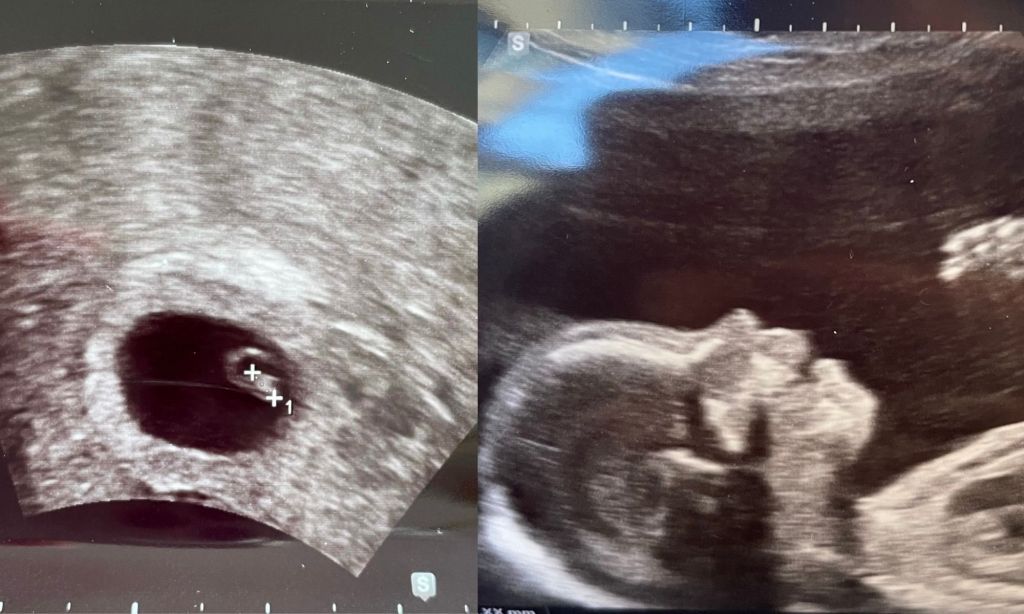

With each sonogram, I’ve felt more and more in-tuned with the change going on inside of me. Although she was only a few millimeters big, I held her very first picture in my hands. From a poppy seed to the size of a papaya, each gyno visit has been pretty mind-blowing.